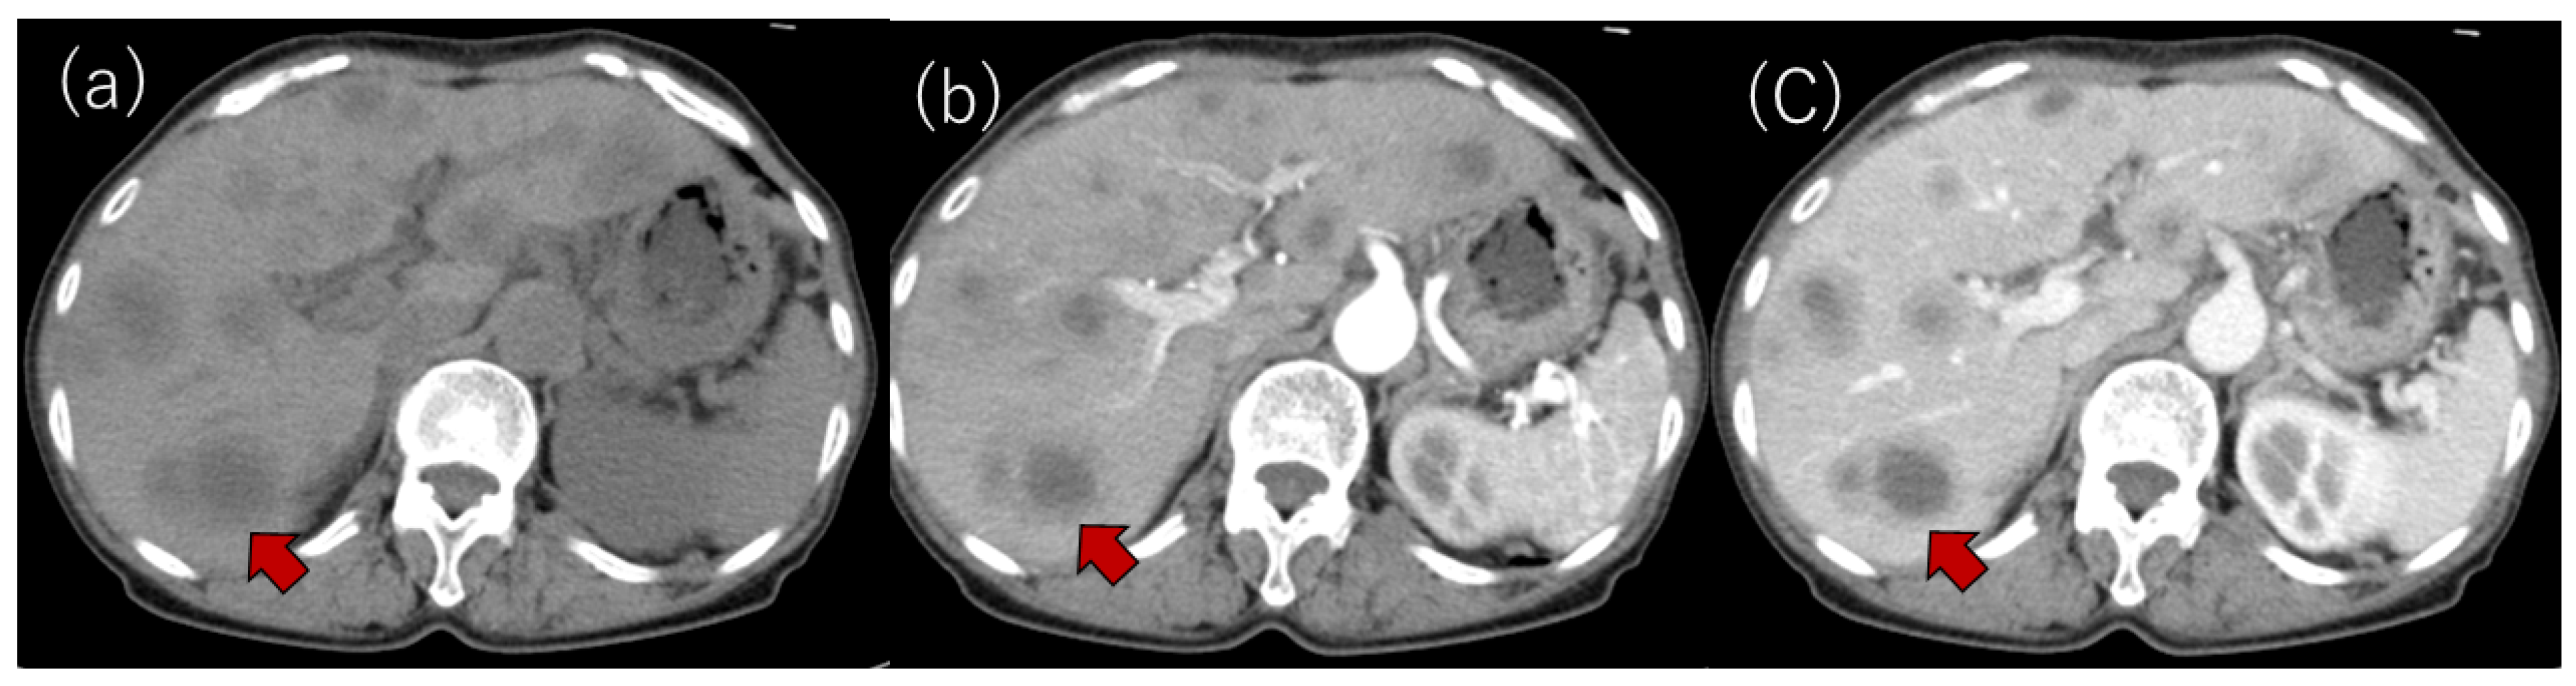

Laboratory examinations (Table 1) showed mild elevation of the serum aspartate aminotransferase and C-reactive protein (CRP) levels. The peripheral blood data, including the white blood cell count and platelet count, and the prothrombin time were found to be within the normal range. Tumor markers, such as carcinoembryonic antigen (CEA), carbohydrate antigen 19-9 (CA19-9), α-fetoprotein (AFP) and protein induced by vitamin K absence or antagonist-II (PIVKA-II), were within the normal ranges. Contrast-enhanced computed tomography (CE-CT) showed low-attenuation areas with mild peripheral enhancement at the arterial and portal phase (Figure 2), suggesting the development of metastatic liver tumors. However, no primary tumor candidate was found on the CE-CT. Esophagogastroduodenoscopy and colonoscopy did not reveal any malignant disease. In addition, despite the presence of suspected metastatic tumors on the US and CT, 18F-fluorodeoxyglucose positron emission tomography with CT (FDG-PET/CT) showed no significant uptake in the tumors (Figure 3).

In our case, CE-CT showed low-attenuation areas in the center of the tumors (Figure 2). However, at the early vascular phase of CEUS, the tumors were shown as very slight hypoenhancement with some hypervascular parts. These CEUS findings were inconsistent with those of metastatic liver tumors, which have internal necrosis. Malignant lesions reportedly show a high intensity on DWI and hypo-values on ADC because of their high cell density [24,25]. Regarding the MRI findings in our case, the DWI showed high-intensity lesions; however, high values were observed on the ADC maps. In addition, the FDG-PET showed a normal standardized uptake value for the tumors. These results were atypical for metastatic tumors.

Figure 2. (a) Plain CT. Multiple low-attenuation areas were detected; (b,c) contrast-enhanced CT revealed multiple low-attenuation areas with mild peripheral enhancements at the arterial (b) and portal phases (c). A typical tumor is shown with an arrow in each panel.